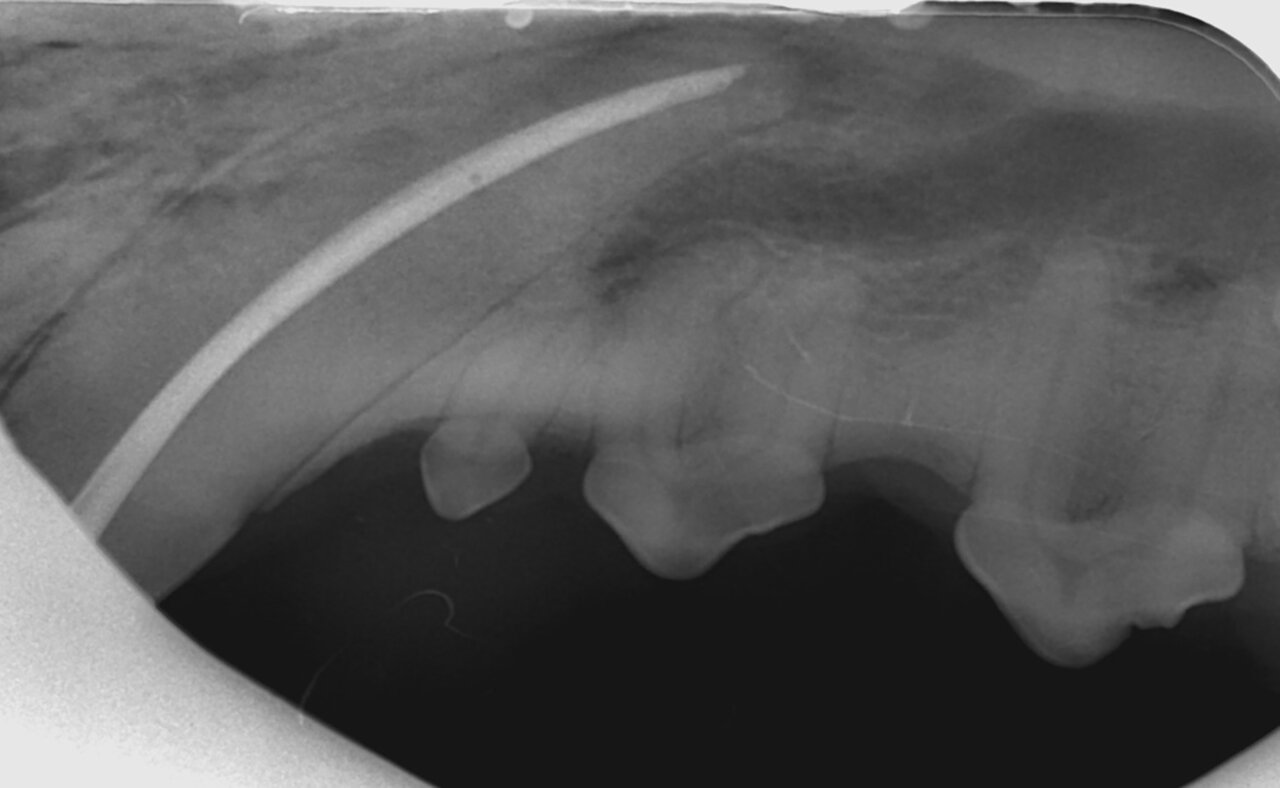

Además de permitirnos evaluar el grado de enfermedad periodontal, también hace posible seleccionar el mejor tratamiento en función de su patología y las posibles complicaciones, como las fracturas mandibulares iatrogénicas en perros de talla pequeña con enfermedad periodontal PD4 (imágenes 10 y 11).